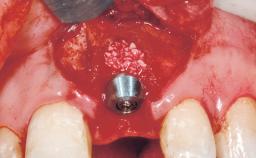

Immediate Flapless Placement of an Implant in a Maxillary Left Central Incisor Site

| Type of Implants | One-Piece |

| Attachment | One-Piece |

| Placement Protocol | Immediate implant placement |

| Tooth Site | Maxillary incisor or canine |